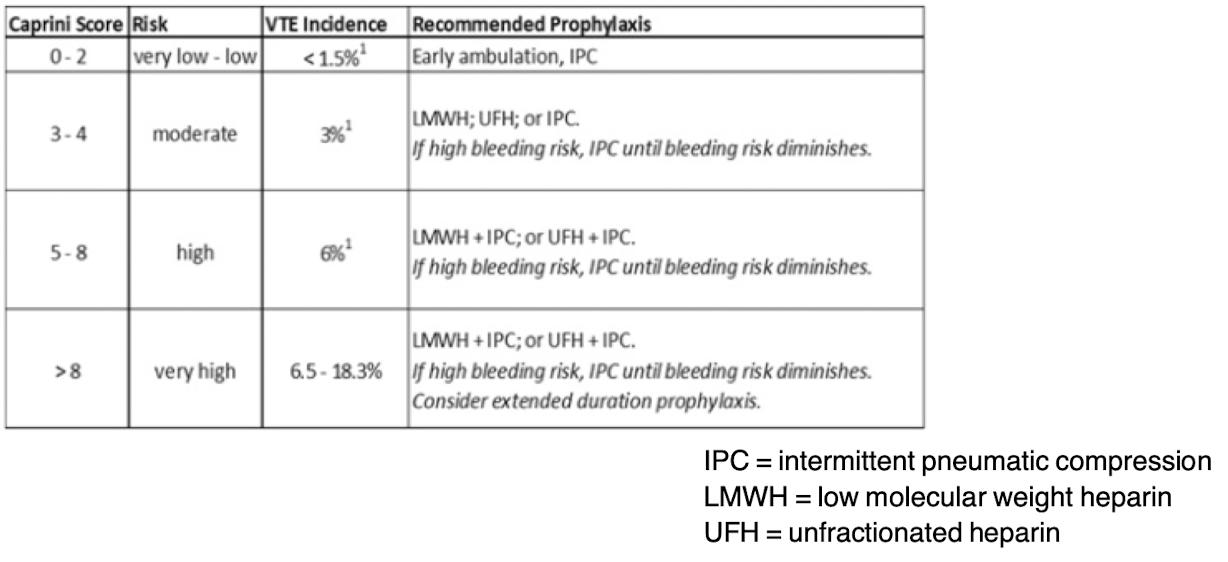

Caprini Model

What is the preoperative risk assessment for VTE for use in all elective general surgery patients?

Caprini Score

-Assess with ___________ for VTE risk

-Virchow’s Triad risk factors: Immobilization, Cancer, Pregnancy, Critical illness, Surgery, Smoking, Obesity, Trauma, OCPs, prior VTE

Prophylaxis:

• Ambulation, TED hose

• SCDs (sequential compression devices)

• LMWH (low molecular weight heparin), Heparin

**evaluate meds DAILY and change as indicated

FASTHUGSBID- Thromboprophylaxis